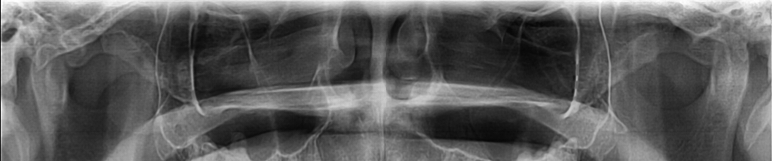

파노라마 사진보고 비중격만곡증 있는지 확인 가능한가요?

현재 파노라마 뷰 및 두개골 xray사진만으로는 정확히 비중격 만곡증을 확인할 수 없습니다. 직접 진료를 통해 확인하거나 CT 사진을 확인하는 것이 정확한 진단에는 도움이 될 수도 있으니 해당과 전문의에게 먼저 진료를 받으시는 것이 좋겠습니다.

비중격 만곡은 X-ray 파노라마 사진만으로는 감별이 어렵습니다.

비중격이 우측으로 치우쳐 비강의 크기가 달라보이지만 실제 신체진찰도 함께 병행되어야 감별이 가능합니다.

엑스레이 검사를 통해서는 비중격에 대한 정확한 평가가 가능하지 않습니다. 올리신 엑스레이 사진에서는 딱히 비중격만곡증을 의심할만한 소견은 보이지 않지만 그렇다고 하여 완전히 배제할 수는 없습니다. CT와 같은 더 정밀한 검사를 확인할 필요가 있습니다.